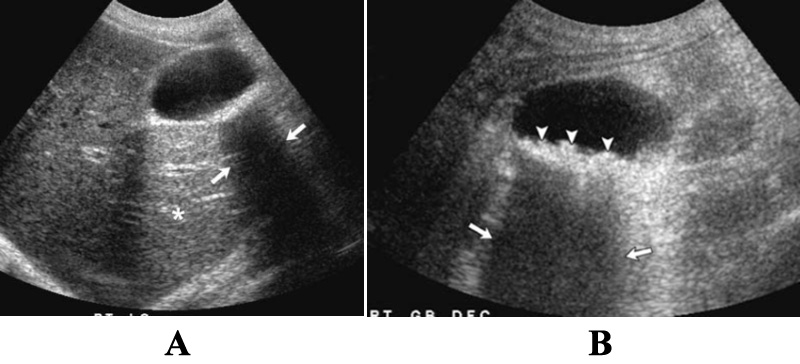

Рисунок 1. УЗИ мочевого пузыря. Стрелками указан участок реверберации в передних отделах мочевого пузыря

Рисунок 5. УЗИ желчного пузыря: акустическое затенение. А – камни в желчном пузыре идентифицируются по четкой звуковой тени (см стрелки); данный пациент находится в положении лежа на спине, что не позволяет обнаружить все камни (такое предположение сделано на основании тени). Кроме этого нужно обратить внимание на акустический эффект усиления позади желчного пузыря (отмечено звездочкой). В – УЗИ желчного пузыря того же пациента в положении лежа на боку: определяются множественные эхогенные тени (указатели), за которыми хорошо определяется тень (стрелки)